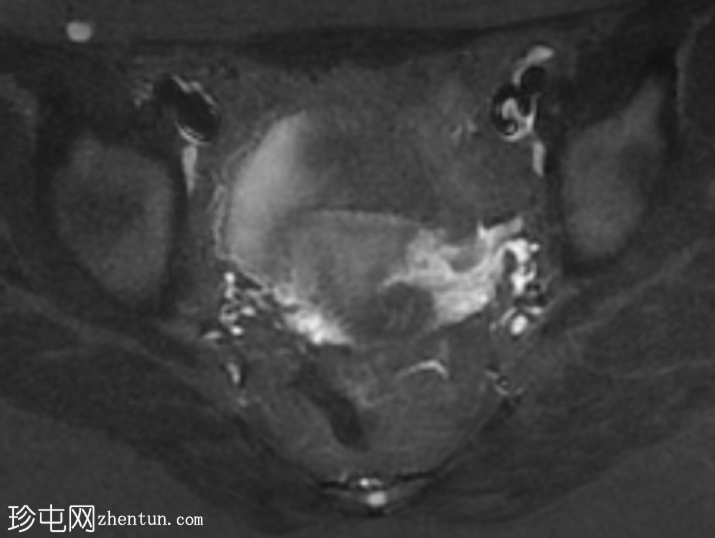

轴位

T1加权像

子宫体积较小,最大横径、前后径和头尾径均为3.0 x 3.0 x 2.7 cm。子宫体与宫颈的比例为1.3:1。子宫无明显分区结构。

双侧卵巢发育不良,无卵泡活动。